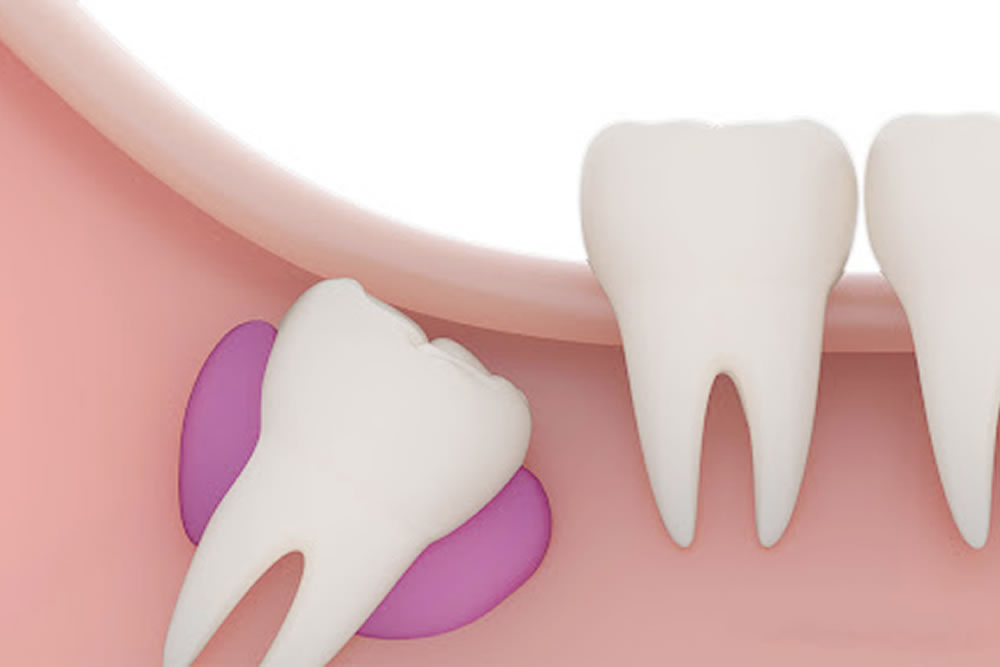

歯並びに悪影響を及ぼす可能性がある

横向きや斜めに生えている親知らずは、手前の歯を押してしまうことがあります。その影響で歯が少しずつ動き、歯並びや噛み合わせが乱れてしまう可能性があります。将来のトラブルを防ぐためにも、早めの抜歯をご提案することがあります。